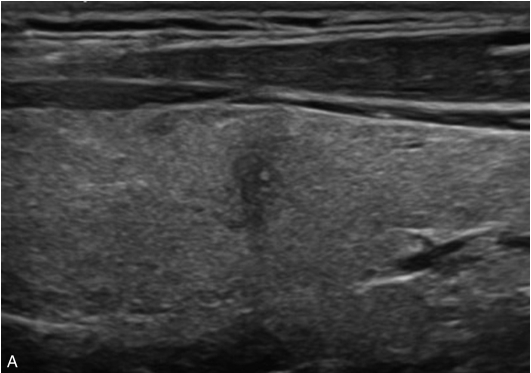

男性31岁,超声发现甲状腺结节2年余,无不适。既往右侧颈前区可扪及3cm×2cm包块,质韧,无压痛,可随吞咽动作运动。2年内自觉颈前区包块逐渐缩小,1年前包块消失。

第一次常规超声检查:甲状腺右叶形态失常,中部可见一个类椭圆形混合回声结节,大小约2.5cm×2.2cm×2.4cm,边界清楚,形态规则,内部回声不均匀,以无回声为主,内见稍低回声实性成分,后方回声增强。CDFI显示结节周边可见少量点条状血流信号,内部无回声区及实性成分均未见血流信号,见图1-3-13。

第二次常规超声检查:甲状腺右叶形态基本正常,中部见一个低回声结节,大小:0.5cm×0.7cm×0.5cm,边界欠清,边缘不规则,纵横比>1,内部回声不均匀,可见小片状强回声,后方回声衰减。结节大小较第一次超声检查明显缩小。CDFI显示结节边缘可见点状血流信号,内部未见血流信号,见图1-3-14。

图像描述:甲状腺右叶中部结节增强早期大部分无增强,仅见内部线样等增强;增强晚期内部线样增强逐渐廓清,全结节呈无增强,见图1-3-15、ER1-3-7。

图1-3-13 甲状腺右叶结节第一次常规超声检查

A.甲状腺右叶结节灰阶超声图像;B.甲状腺右叶结节CDFI超声图像

图1-3-14 甲状腺右叶结节第二次常规超声检查

A.甲状腺右叶结节灰阶超声图像;B.甲状腺右叶结节CDFI图像